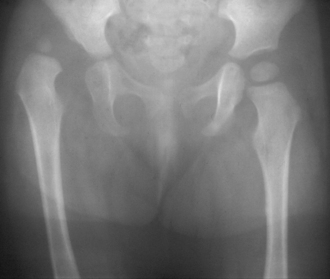

Hip Dysplasia

This is a congenital hipjoint anomaly that causes the child to keep the entire affected limb in a peculiar position, you may also hear a clicking sound from hip if you try to move the limb form that position.

What to do?

This condition is best managed within 6 months of age, and often become really difficult to cure in older age groups. You should consult your orthopaedician for consultation of proper management protocol of this problem as soon as u suspect it. From complete cure to disability remaining upto adulthood, this condition has a wide range of prognosis depending on the severity.